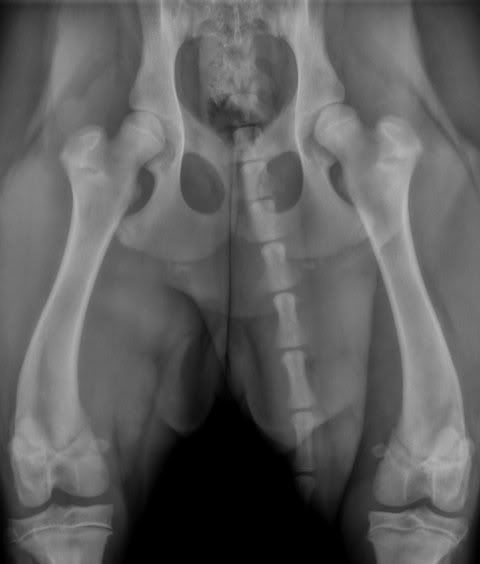

De eerste foto is van een 6 maanden oude labrador, die een vreemd loopje heeft en mankt. Gezien het ras en het vreemde loopje een röntgenfoto genomen:

Deze heupen zien er prima uit. Uiteraard zegt dat nog niet dat ze op 18 maanden leeftijd nog steeds perfecte heupen heeft, ze is nu nog te jong en bovendien is de röntgenfoto niet goed genoeg genomen om dat met zekerheid te kunnen zeggen. Wel is volstrekt duidelijk dat het manken niet door de heupen komt (ze bleek de kruisbanden van beide knieën gescheurd te hebben, wordt volgende week waarschijnlijk geopereerd). Zelfs als de heupen later toch achteruit gaan is het ondenkbaar dat zij ooit een bekkenkanteling nodig zou hebben.